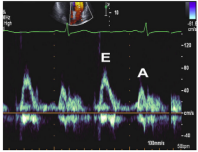

8、二尖瓣口舒张期血流频谱指标1

●Valsalva 动作E/A比值 (1.3—0.6):E/A比值减少≥50%对提示LV充盈压增高具有高度特异性,但是变化幅度较小并不提示舒张功能正常。

●当二尖瓣口血流及二尖瓣环速度测量仍不能确定病人的舒张功能时,Valsava动作还是可以作为一种保留的检查手段。

9、二尖瓣口舒张期血流频谱指标2

10、二尖瓣环运动速度指标

左室舒张功能受损

①室间隔侧e’< 7 cm/s;

②侧壁侧e’< 10 cm/s;

③平均E/e’> 14